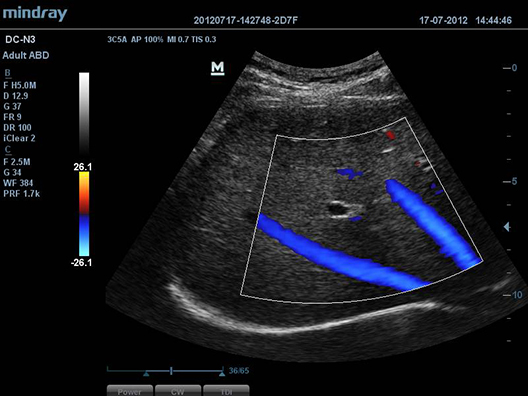

iScapeTM

–î–∞–µ—Ç –ø–æ–ª–Ω—ã–π –∏ —Ä–∞—Å—à–∏—Ä–µ–Ω–Ω—ã–π –æ–±–∑–æ—Ä –∞–Ω–∞—Ç–æ–º–∏—á–µ—Å–∫–∏—Ö —Å—Ç—Ä—É–∫—Ç—É—Ä –ø–æ—Å—Ä–µ–¥—Å—Ç–≤–æ–º –ø–∞–Ω–æ—Ä–∞–º–Ω–æ–π –≤–∏–∑—É–∞–ª–∏–∑–∞—Ü–∏–∏, –≤ —Å–æ—á–µ—Ç–∞–Ω–∏–∏ —Å –∏–Ω–¥–∏–∫–∞—Ç–æ—Ä–æ–º —Å–∫–æ—Ä–æ—Å—Ç–∏ –∏ —Ñ—É–Ω–∫—Ü–∏–µ–π –ø—Ä—è–º–æ–≥–æ / –æ–±—Ä–∞—Ç–Ω–æ–≥–æ —Å–∫–∞–Ω–∏—Ä–æ–≤–∞–Ω–∏—è, –¥–µ–ª–∞—è –ø—Ä–æ—Ü–µ—Å—Å –±–æ–ª–µ–µ –ª–µ–≥–∫–∏–º, –ø–æ—Å–ª–µ–¥–æ–≤–∞—Ç–µ–ª—å–Ω—ã–º –∏ —É–ø—Ä–∞–≤–ª—è–µ–º—ã–º.